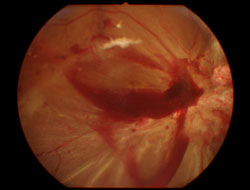

3、出血量少的患者可以看到视网膜的原发性疾病,但出血量大的患者无法看见眼底病变,甚至仅能看见红黑色的反光。